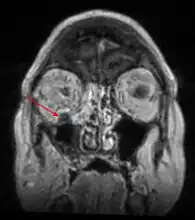

Imaging is often performed, such as CT scan of lungs and sinuses.[38] Signs on chest CT scans, such as nodules, cavities, halo signs, pleural effusion and wedge-shaped shadows, showing invasion of blood vessels may suggest a fungal infection, but does not confirm mucormycosis.[16] A reverse halo sign in a person with a blood cancer and low neutrophil count, is highly suggestive of mucormycosis.[16] CT scan images of mucormycosis can be useful to distinguish mucormycosis of the orbit and cellulitis of the orbit, but imaging may look identical to those of aspergillosis.[16] MRI may also be useful.[39]

MRI head: right sided sinus involvement extending into the orbit. -